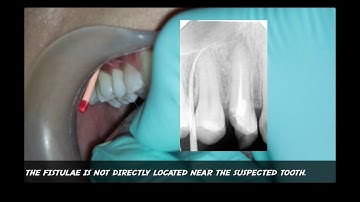

Tracing Sinus Tract With Gutta Percha Point TAKEN WITH XRAY IMAGE